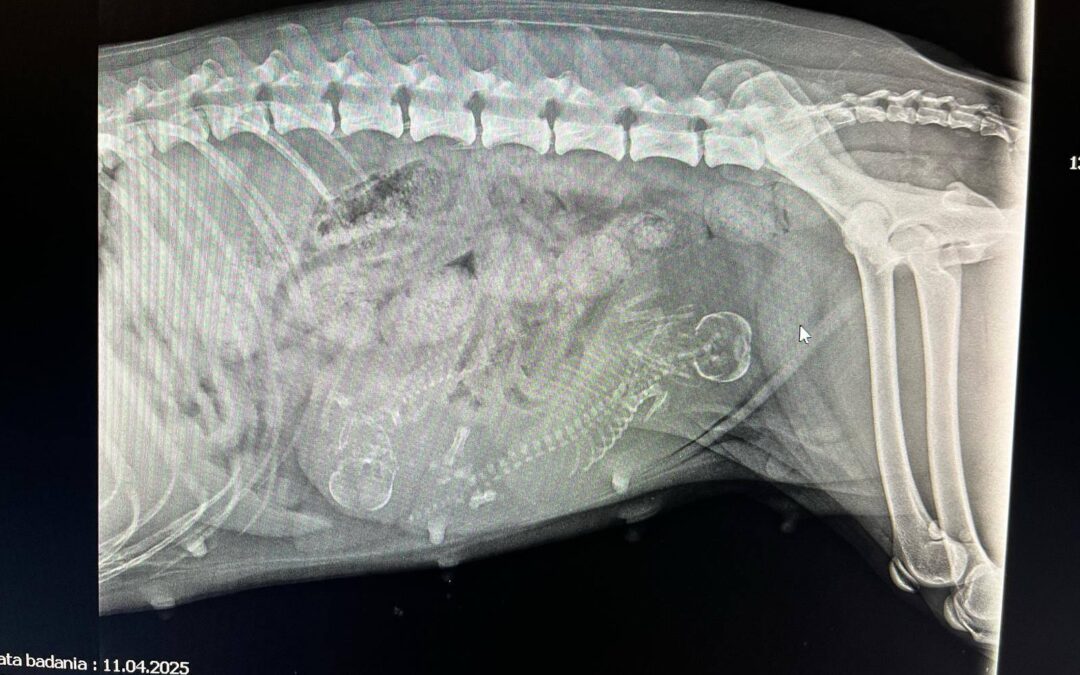

Dzisiaj odwiedziliśmy klinikę weterynaryjną SkaVet na zrobienie zdjęcia i sprawdzenie stanu ciąży. Ku wszystkich zaskoczeniu i wielkości Sigi okazuje się, że będą dwa bąbelki.